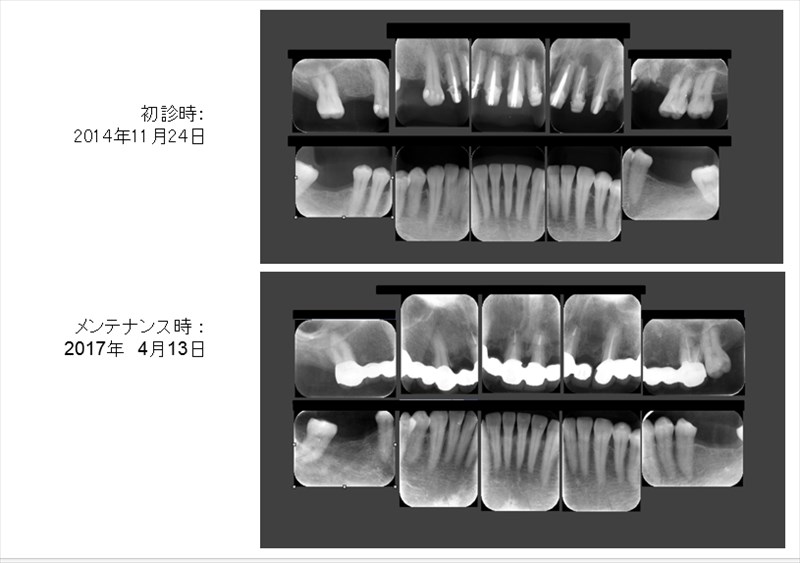

術前のレントゲンでは根尖病変(根の先に膿が溜まっている状態)が確認され、そこに垂直的な骨欠損があり7mmのポケットがありました。右のレントゲンを見て頂くと骨が再生しポケットは2mmに。根尖病変(根の先に膿が溜まっている状態)も改善されています。この症例は歯周病の再生療法と精密根管治療どちらのクオリティーが落ちても上手くいかない症例です。

勿論全体的に歯周病や虫歯も治り良く食べられるとおっしゃって頂けました。